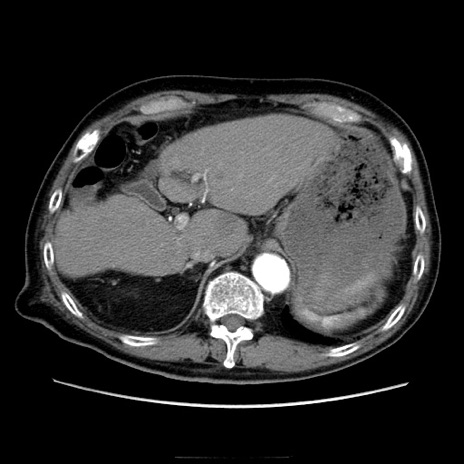

症例21(横断像)

【症例】70歳代男性

【主訴】腹痛

【現病歴】肝硬変・肝細胞癌にてかかりつけの方。約9時間前に食後より腹痛出現。症状が徐々に増悪し、嘔吐出現したため来院。

【既往歴】肝硬変、肝細胞癌(RFA、TACE後)

【身体所見】意識清明、表情苦悶様、BT 36℃、BP 129/78mmHg、P 88bpm、SpO2 97%(RA)、右上腹部から心窩部にかけて圧痛あり、反跳痛なし、筋性防御あり。

【データ】WBC 5800、CRP 0.16